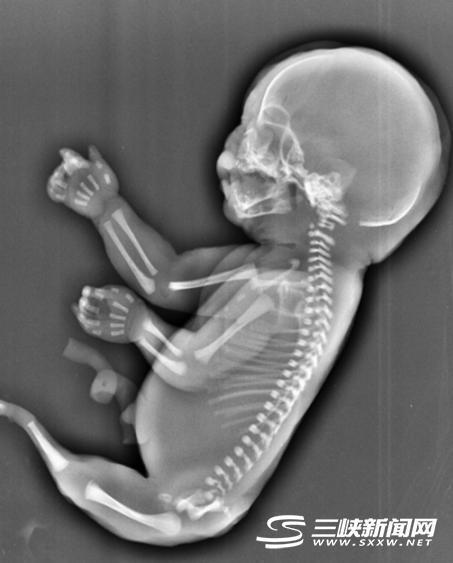

吴女士当时经超声检查发现,孕妇宫腔内未见羊水暗区,借助胎儿骨骼影像顺序连续扫查,发现胎儿头颅、胸腔、双上肢,也可以看到一个跳动的心脏。但下肢只找到一条股骨,未见双腿、膀胱,只有一侧发育不良的肾脏。

美人鱼综合症是一种极其罕见的先天性下肢畸形疾病,6万-10万人中才有1例,患病的新生儿出生后只能够存活几个小时。 关于其病因至今仍是个谜,但医学专家认为可能和遗传基因有关。已知的美人鱼综合症幸存者只有2人,存活率极低。